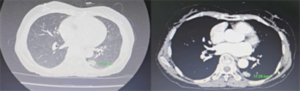

Ca lâm sàng: Điều trị miễn dịch phối hợp hóa chất cho bệnh nhân ung thư phổi di căn hạch tiến triển tại Trung tâm Y học hạt nhân và Ung bướu – Bệnh viện Bạch Mai GS.TS. Mai Trọng Khoa, PGS.TS.Phạm Cẩm Phương, ThS.BSNT.Phạm Minh Lanh, BSNT.Nguyễn Bảo Linh...